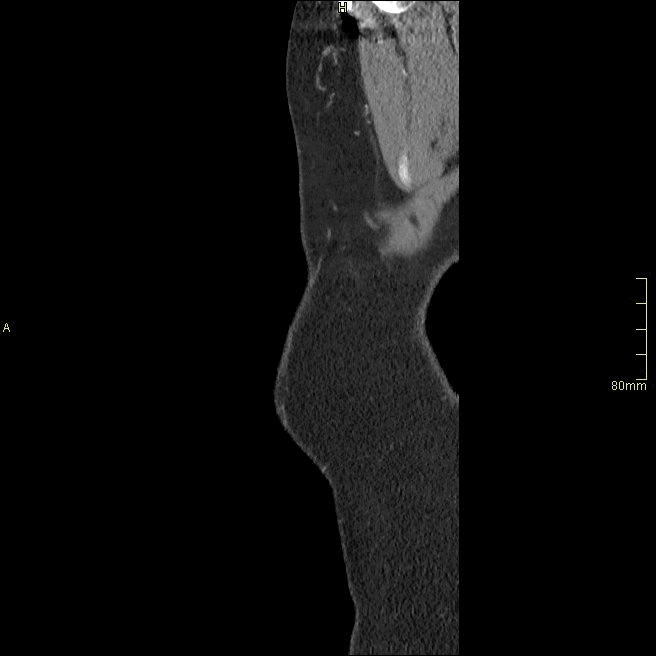

Chest/Abdomen Angiogram (Sagittal)